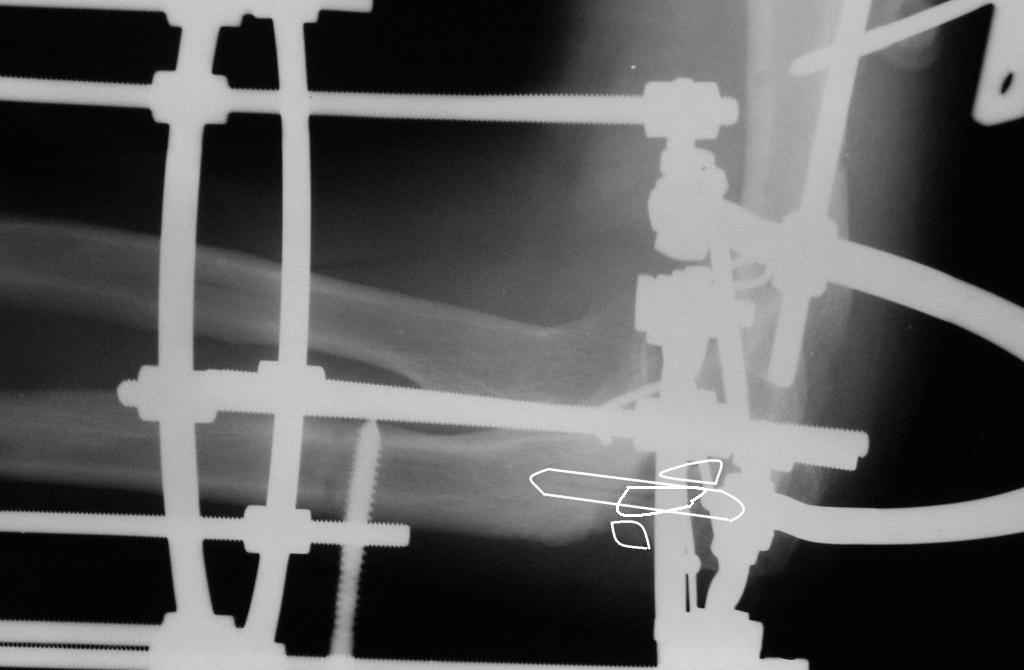

Коллеги! Сделан первый этап операции - синтез спице-стержневым аппаратом. При умеренной дистракции локтевого сустава (0,5 мм в сутки) производится дорзальная тракция дистального отломка локтевой кости (1 мм в сутки) стержнем Штеймана при стабилизации olecranon отдельным стержнем. Стержень в olecranon ввелся очень легко - остеопороз. Р-граммы через 4 дня после операции.